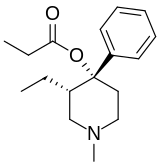

4-Phenylpiperidines

Prodines

- Allylprodine

- (α/β)-Meprodine

- Desmethylprodine (MPPP)

- PEPAP

- (α/β)-Prodine

- Prosidol

- Trimeperidine (promedol)

Structures